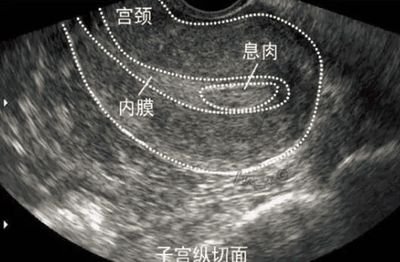

超声监测排卵:通过B超动态观察卵泡的发育和排出情况,是最直观的方法。